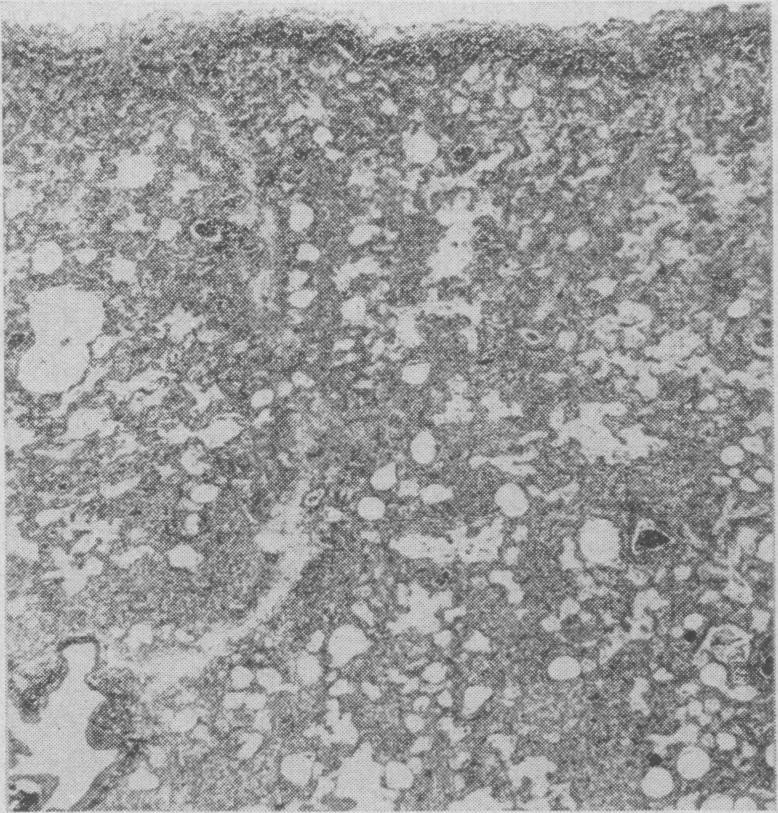

Pulmonary complications during treatment with hexamethonium.

Can Med Assoc J. 1955 Mar 15;72(6):448-51.